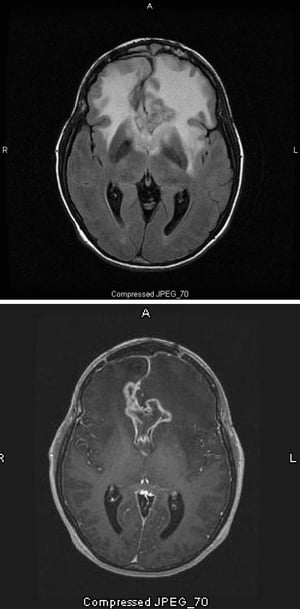

La scansione RM T2-FLAIR (fluid-attenuating inversion recovery) (in alto) mostra un grande segnale bianco bilaterale (iperdensità) attorno al glioblastoma, che è l’astrocitoma con il più alto grado di malignità. Questo particolare glioblastoma è chiamato glioma a farfalla perché il segnale bianco attorno al tumore forma le ali della farfalla; è causato da edema cerebrale. Nella scansione pesata in T1 (in basso), il contrasto delinea il bordo del tumore (enhancement dell'anello). L'edema appare come un'area scura (ipointensità) al T1.

Images courtesy of William R. Shapiro, MD.